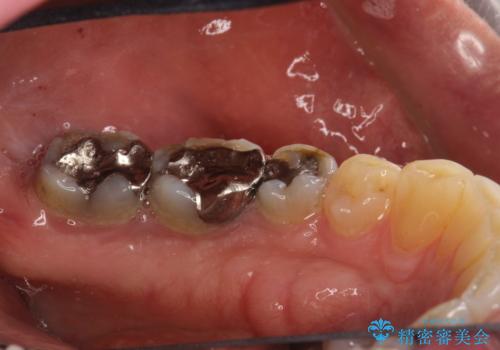

- 歯と歯の間の歯石が気になるとのことで来院されました。PMTC30分コースを行いました。プラークコントロールも悪かったため、歯ブラシ指導も行いました。